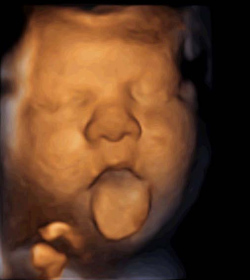

Escucharás el sonido del corazón de tu bebé en la consulta mediante la ecografía del tercer trimestre. La imagen ecográfica te muestra al bebé por partes y cada vez te resultará más difícil identificarle, porque la cabeza, el abdomen o las piernas ocupan toda la pantalla del ecógrafo. Puedes ver con claridad sus bostezos o cómo saca la lengua si la posición de la cara es la idónea.